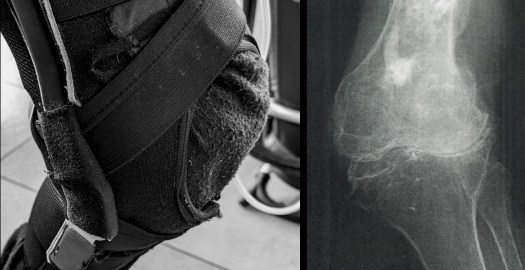

平行棒を握る際の立ち位置は少し離れて実施。懸垂のように腕で身体を引き上げる力をできるだけ排除するのが目的です。足底の意識を高める為に裸足が望ましいですが、汚れを嫌う方には靴下の状態でおこないます。

X脚状態で関節間にゆとりの無い方へのスクワットとして、足底を意識した筋力強化は大腿四頭筋にメインにするのではなく、足底から脚全体への力の入り方に違いを実感されていました。